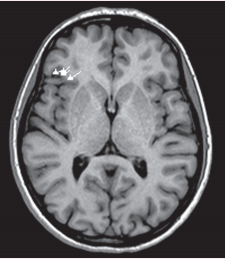

图示:脑磁图显示在右额下回有一簇病灶。本例患者在脑磁图簇区进行了切除,已使癫痫发作消失。白色的三角形和线条表示脑磁图上的尖峰位置。